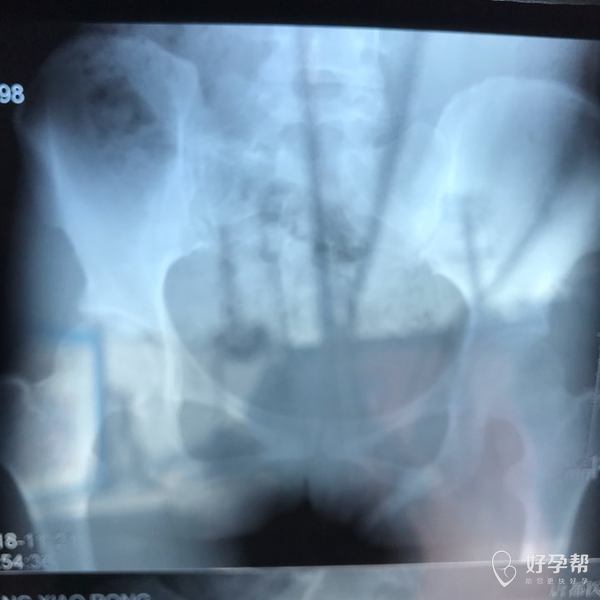

麻烦各位教授给我看看输卵管造影片子,谢谢了🙏

您好,输卵管堵塞,建议切除输卵管做试管,保守保守治疗没有多大意义,觉着我的回复对您有帮助记着帮忙点击采纳,谢谢!